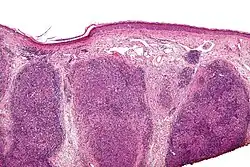

| Low magnification micrograph of a lymphoepithelioma-like carcinoma showing the characteristic squamoid nests in association with clusters of lymphocytes. H&E stain. | |

Lymphoepithelioma-like carcinoma (LELC) is a medical term referring to a histological variant of malignant tumor arising from the uncontrolled mitosis of transformed cells originating in epithelial tissue (or in cells that display epithelial characteristics) that bear microscopic resemblance to lymphoepithelioma (nasopharyngeal carcinoma).

There is considerable variation in the classification of LELC—while it is perhaps most commonly considered a subtype of squamous cell carcinoma, it can also be classified as a form of large cell carcinoma (i.e. when occurring in the lung),[1] and can be considered as a separate, unique entity.[2]